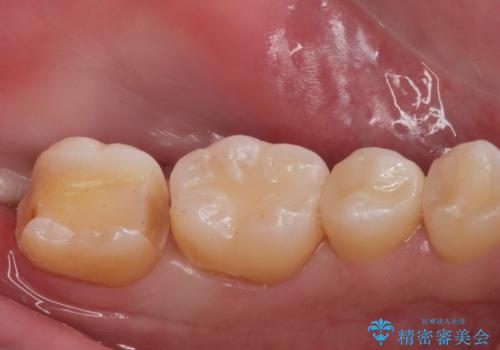

e-maxインレーによる治療

- 定期検診で来院してレントゲンを撮ったところ

歯と歯の間にう蝕ができていました。

拡大鏡下でう蝕を全て除去してe-maxインレーにて治療を行いました。